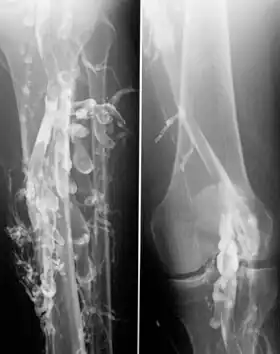

![]() Venography in a patient with deep vein thrombosis | |

Venography (also called phlebography or ascending phlebography) is a procedure in which an X-ray of the veins, a venogram, is taken after a special dye is injected into the bone marrow or veins. The dye has to be injected constantly via a catheter, making it an invasive procedure. Normally the catheter is inserted by the groin and moved to the appropriate site by navigating through the vascular system.

Contrast venography is the gold standard for judging diagnostic imaging methods for deep vein thrombosis; although, because of its cost, invasiveness, and other limitations this test is rarely performed.[1]